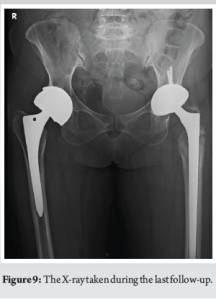

Following comprehensive pre-operative assessment, the patient was scheduled for revision THR on the left side. Intraoperatively, we encountered dark brown synovial fluid, gross black staining of tissues consistent with metallosis, similar to a previous case (Fig. 7). Synovial fluid and tissue samples were sent for histopathological examination, which revealed an aseptic lymphocyte-dominated vasculitis-associated lesion (ALVAL) reaction (Fig. 8). The femoral and acetabular components were revised with ceramic-on-polyethylene implants(Fig 9).